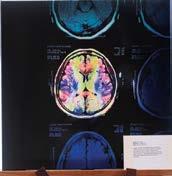

A recent project funded by a RANZCR research grant has shown how AI can be used in predicting brain tumour subtypes.

Arecently completed project in New Zealand has confirmed the potential for artificial intelligence in aiding tumour subtype identification.

This project, led by RANZCR Fellow Dr Hugh McHugh, has seen the development of an AI model to predict brain tumour subtypes from pre-operative MRI of New Zealand hospital patients who were suspected to have diffuse glioma, as well as several large publicly available datasets of MRIs.

Isocitrate dehydrogenase (IDH) mutation and 1p19q codeletion are the most important molecular markers in glioma in terms of survival outcomes. At present IDH and 1p19q status remains unknown until after tumour resection or surgical biopsy. There is growing evidence that it is possible to reliably and non-invasively predict IDH and 1p19q status from preoperative MRI using artificial intelligence (Al).

Dr McHugh’s project follows on from his Master's work, whereby an Al IDH and 1p19q prediction algorithm was retrospectively assessed on large NZ and overseas cohorts with high accuracy. The continuation of the project saw the addition of CNS lymphoma and metastasis to the predictive algorithm. Prof Sandeep Bhuta, a member of the RANZCR Clinical Radiology Research Committee, has confidence in the project, and said, “This topic is of very clinical relevance; glioma management these days is entirely dependent

on genetic and molecular markers and IDH status can only be known by invasive biopsy or debulking of brain tumour. If MRI and AI can noninvasively predict the IDH status it will be very helpful for radiation and medical oncologists.”

The design of the project led to a positive outcome, with confirmation of the AI model’s core functionality to predict molecular subtypes in suspected gliomas. Dr McHugh was successful in obtaining a RANZCR Clinical Radiology Research Grant, to support the writing of specialised software to facilitate the transfer of files to and from PACS, along with an Al capable server.